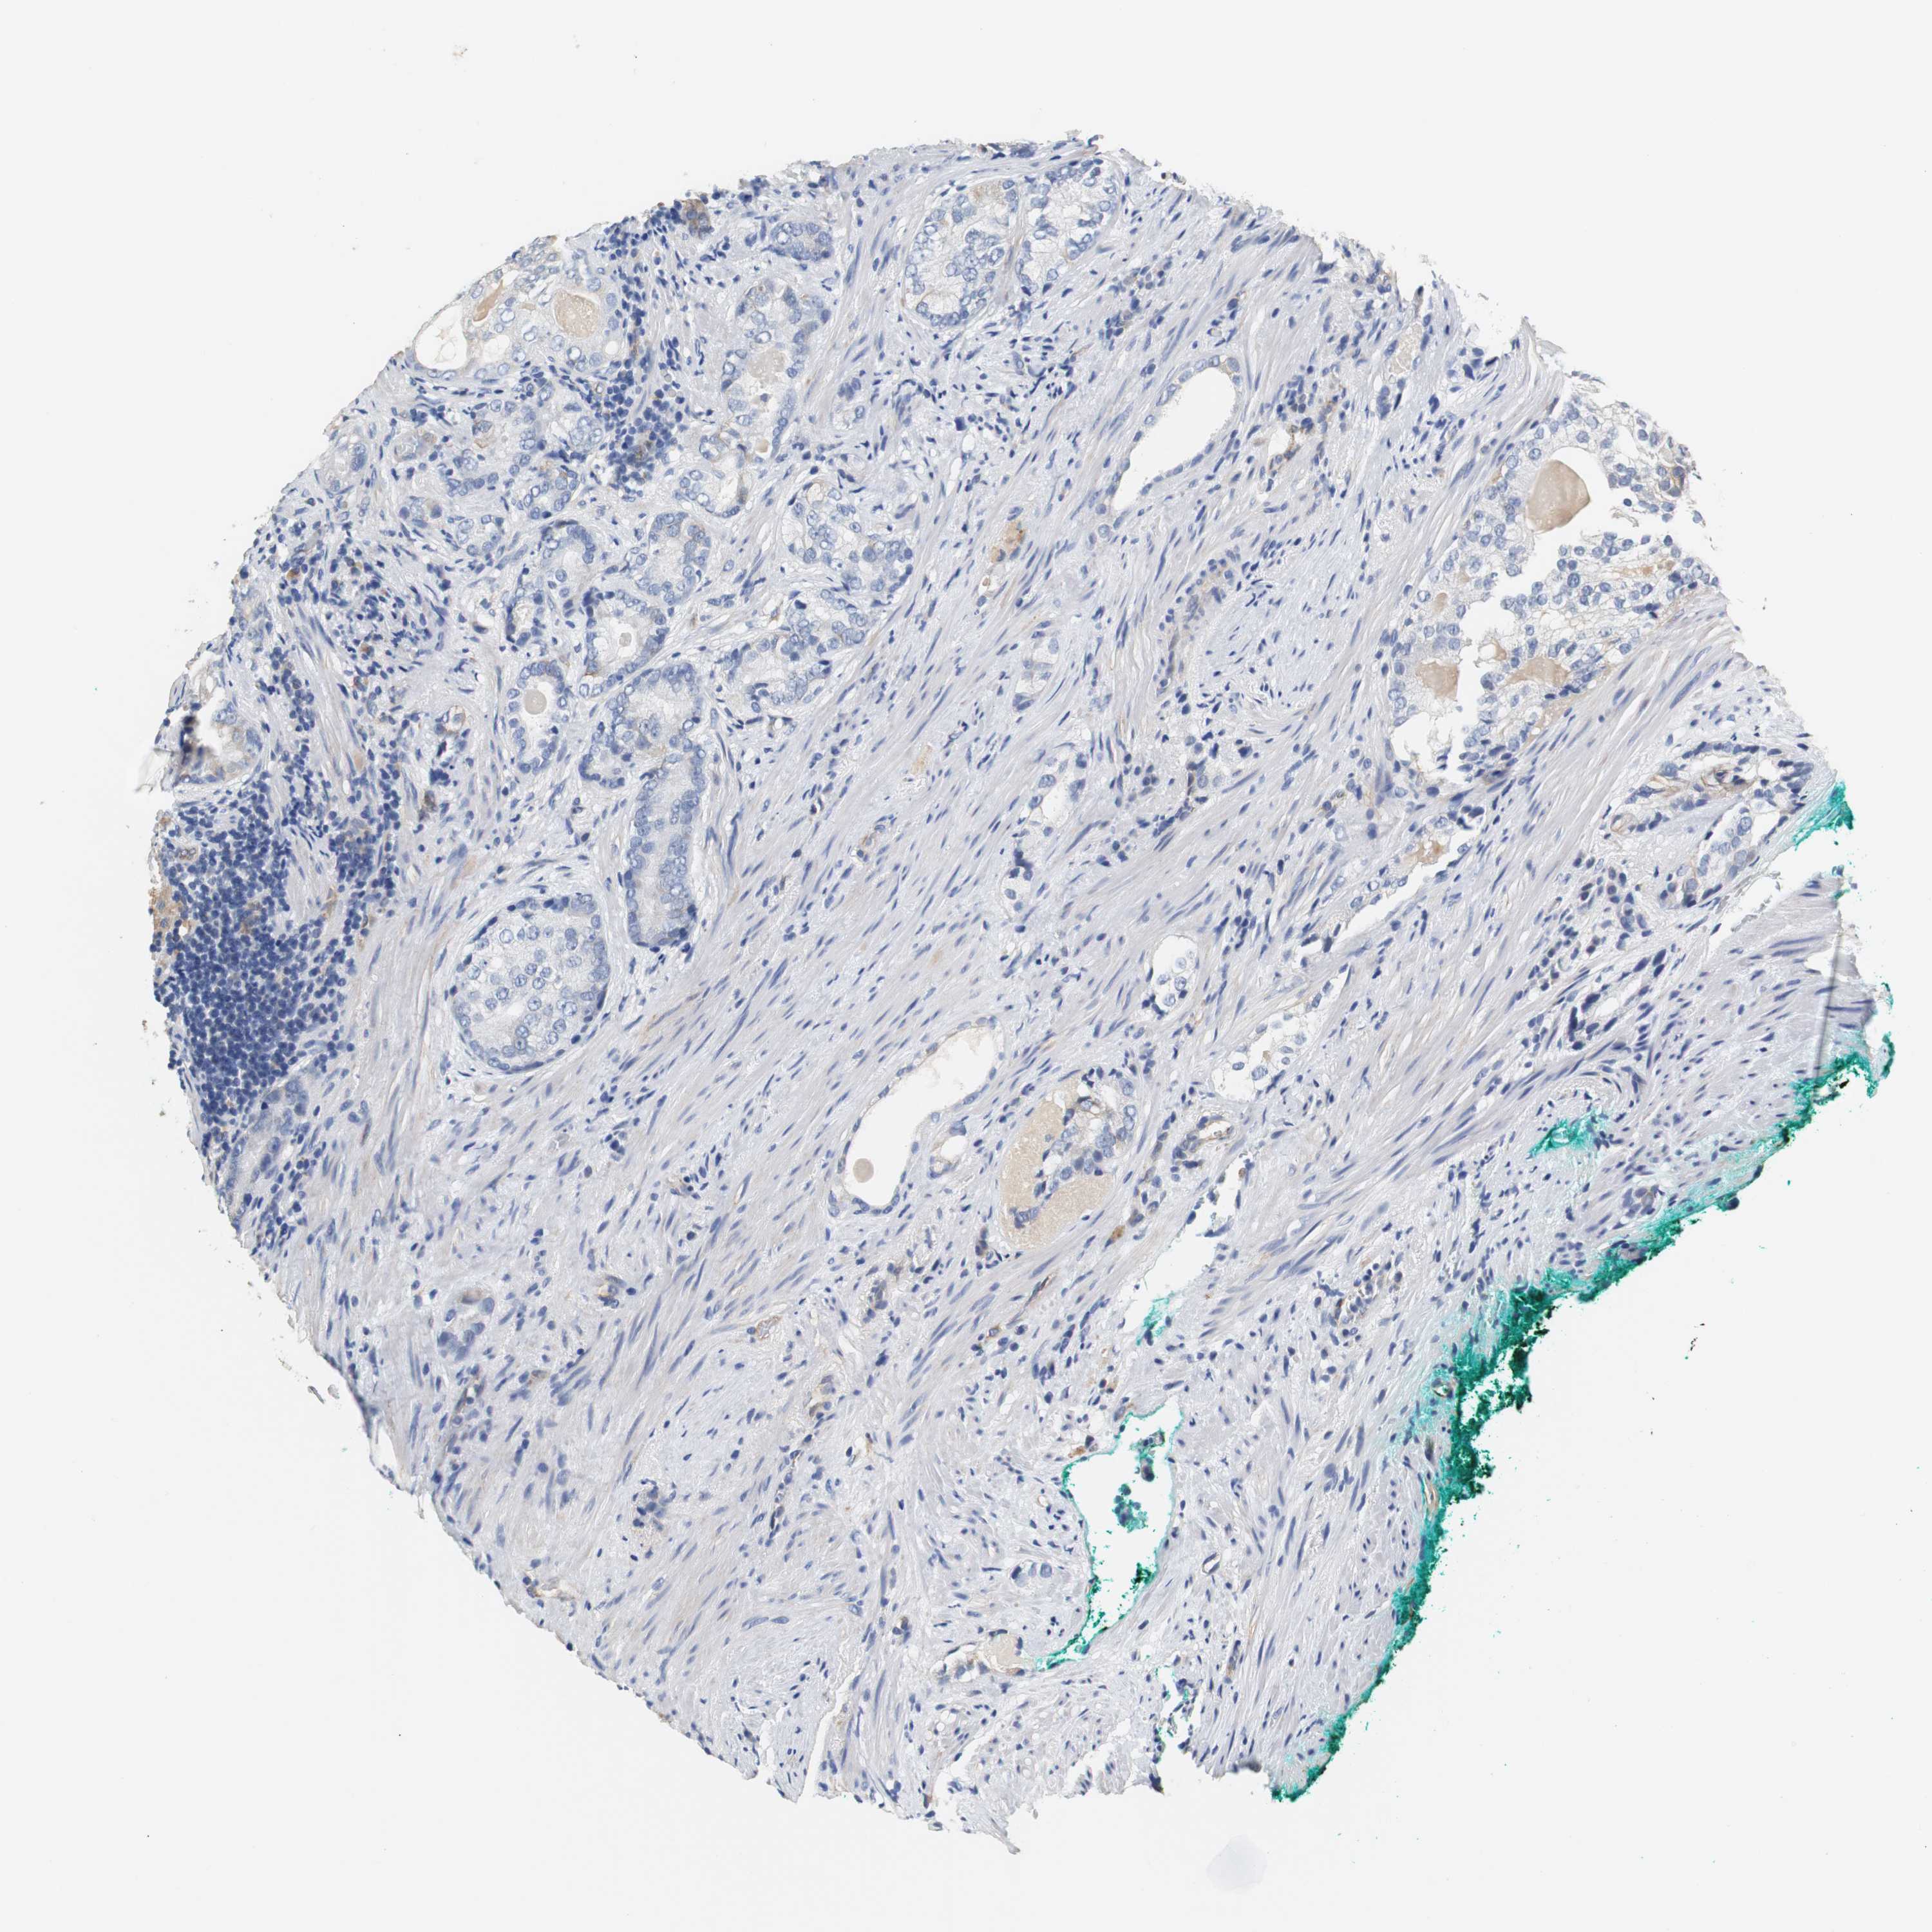

PROSTATE CANCER - Protein expressioni

A mouse-over function shows sample information and annotation data. Click on an image to view it in a full screen mode. Samples can be filtered based on level of antibody staining by selecting one or several of the following categories: high, medium, low and not detected. The assay and annotation is described here.

Antibody stainingi

Antibody staining in the annotated cell types in the current human tissue is reported as not detected, low, medium, or high, based on conventional immunohistochemistry profiling in selected tissues. This score is based on the combination of the staining intensity and fraction of stained cells.

Each image is clickable and will lead to virtual microscopy that enables deeper exploration of all samples and also displays staining intensity scores, fraction scores and subcellular localization as well as patient and tissue information for each sample.

Antibody HPA006277

Antibody HPA006507

Antibody CAB017027

Staining

High

Medium

Low

Not detected

Intensity

Strong

Moderate

Weak

Negative

Quantity

>75%

75%-25%

<25%

None

Location

Nuclear

Cytoplasmic/membranous

Cytoplasmic/membranous,nuclear

Adenocarcinoma, High grade

Adenocarcinoma, Low grade